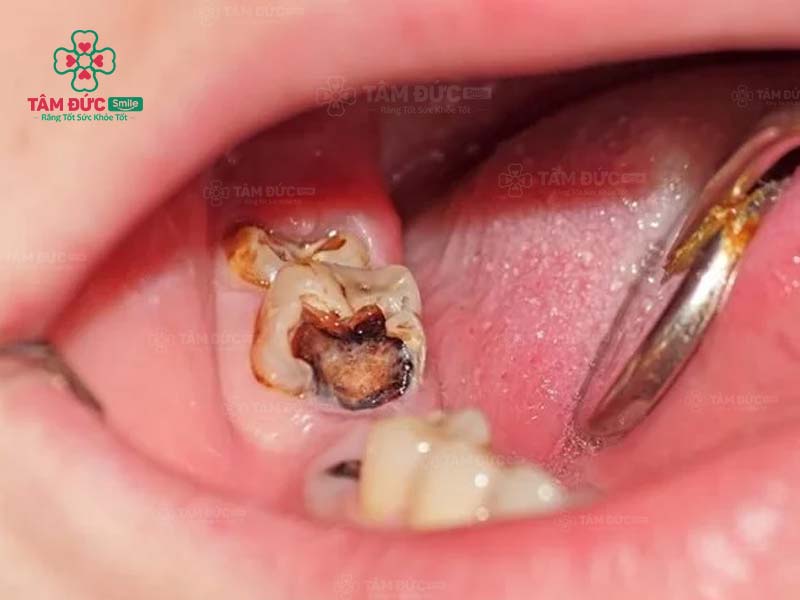

1.1. Răng bị sâu

Khi răng bị sâu, trên thân răng xuất hiện các lỗ nhỏ li ti. Đây chính là vị trí trú ngụ của hàng nghìn loại vi khuẩn. Cùng với thói quen chăm sóc răng miệng không tốt, ăn thực phẩm chứa nhiều đường, lỗ sâu răng sẽ lớn dần và gây đau nghiêm trọng. Nguy hiểm nhất chính là nhiễm trùng và mất răng vĩnh viễn.

Trám răng giúp lấp đầy các lỗ hổng trên thân răng. Nhờ đó, các triệu chứng khó chịu, biến chứng do răng sâu được loại bỏ triệt để. Thẩm mỹ của chiếc răng bị sâu nói riêng và cả hàm răng nói chung đều được phục hồi.